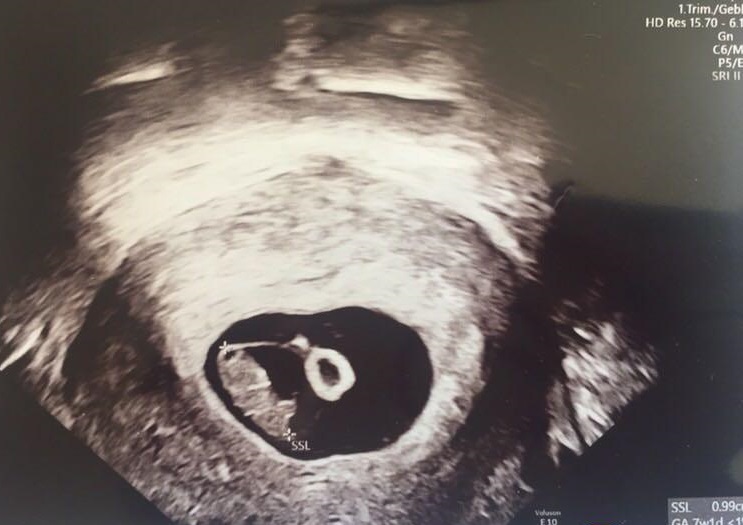

38周+2天,龍鳳寶寶降生,哥哥6斤,妹妹6斤4兩,下面是我做試管和懷孕後的心路歷程囊胚移植5月3日囊胚移植,B超12C合格,現正等待10點囊胚解凍結果,然後11點移植,期待能一切順利!一次好孕,加油;5月7日晚顯水印,8號一天不淡定,測了4次,都差不多比7號的深一點;5月9日早4點半起來又測,感覺比8號深一點點,不知是不是心裡作用,平生第一次測到中隊長,興奮又糾結;5月9日至11日繼續測,感覺已...